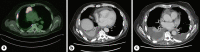

Thymic tumours are rare thoracic malignancies with thymic carcinoma accounting for approximately 12% of all thymic tumours compared to thymomas which account for approximately 86%. Unlike thymomas, it is very rare for thymic carcinomas to be associated with autoimmune disorders or paraneoplastic syndromes. When these phenomena do occur, the vast majority are myasthenia gravis, pure red cell aplasia, or systemic lupus erythematous. Paraneoplastic Sjogren's syndrome is a rare complication of thymic carcinoma, with only two cases previously reported. Here we present 2 cases of patients with metastatic thymic carcinoma who developed autoimmune phenomena consistent with Sjogren's syndrome without classical symptoms prior to treatment. One patient opted for surveillance of their malignancy, while the other underwent chemoimmunotherapy with favourable results. These case reports describe two distinctive clinical presentations of a rare paraneoplastic phenomenon.